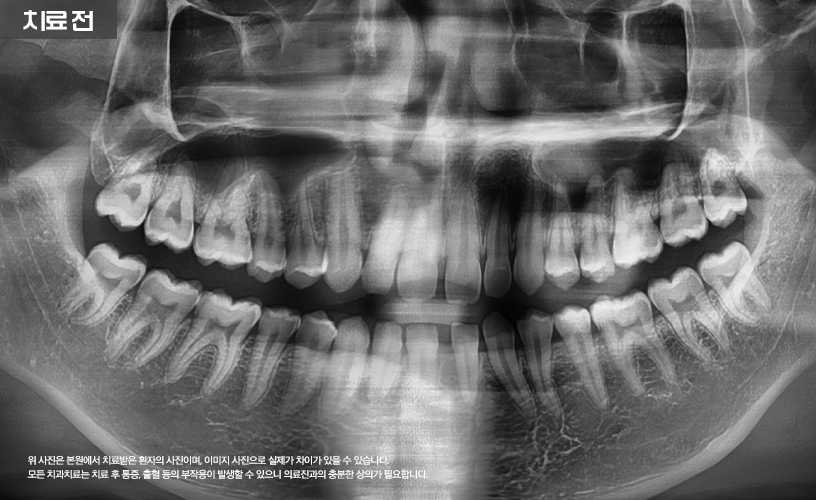

"투명교정 치료 사례"

상기 환자분은 상, 하악 앞니 벌어짐으로 인해

교정 치료를 고민하시다가 본 원에 내원하셨습니다.

본 원에서는 정밀한 검진을 통해 환자분의

앞니 벌어짐 상태를 점검한 다음

기존 일반적인 교정 치료 방식이 아닌

시스루 얼라이너 투명교정 치료가 수립되었습니다.